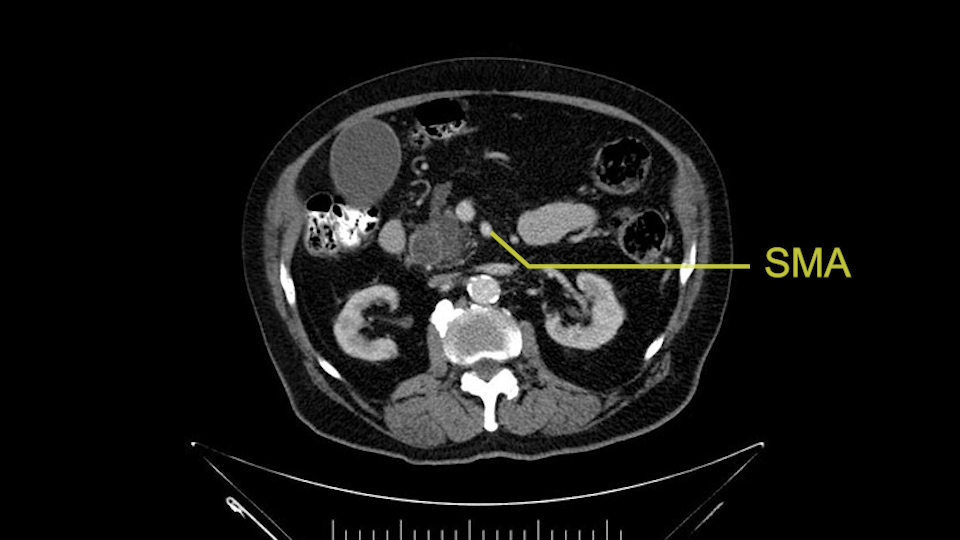

Then either through the coronal or the axial, I’ll do both. Look at the SMA -which is here- I had already looked at it and I don’t see any involvement. There’s the SMA with a nice fat plane between the SMA and the tumor. Over here you can see on the axial, there’s the SMA. Everything on the right side of the SMA has got some nice black around it, which is fat, which means probably no tumor [no tumor, no tumor]. Follow it up to the origin, coming off the aorta. So those are the two technical things that I worry about: the SMA and the SMV.